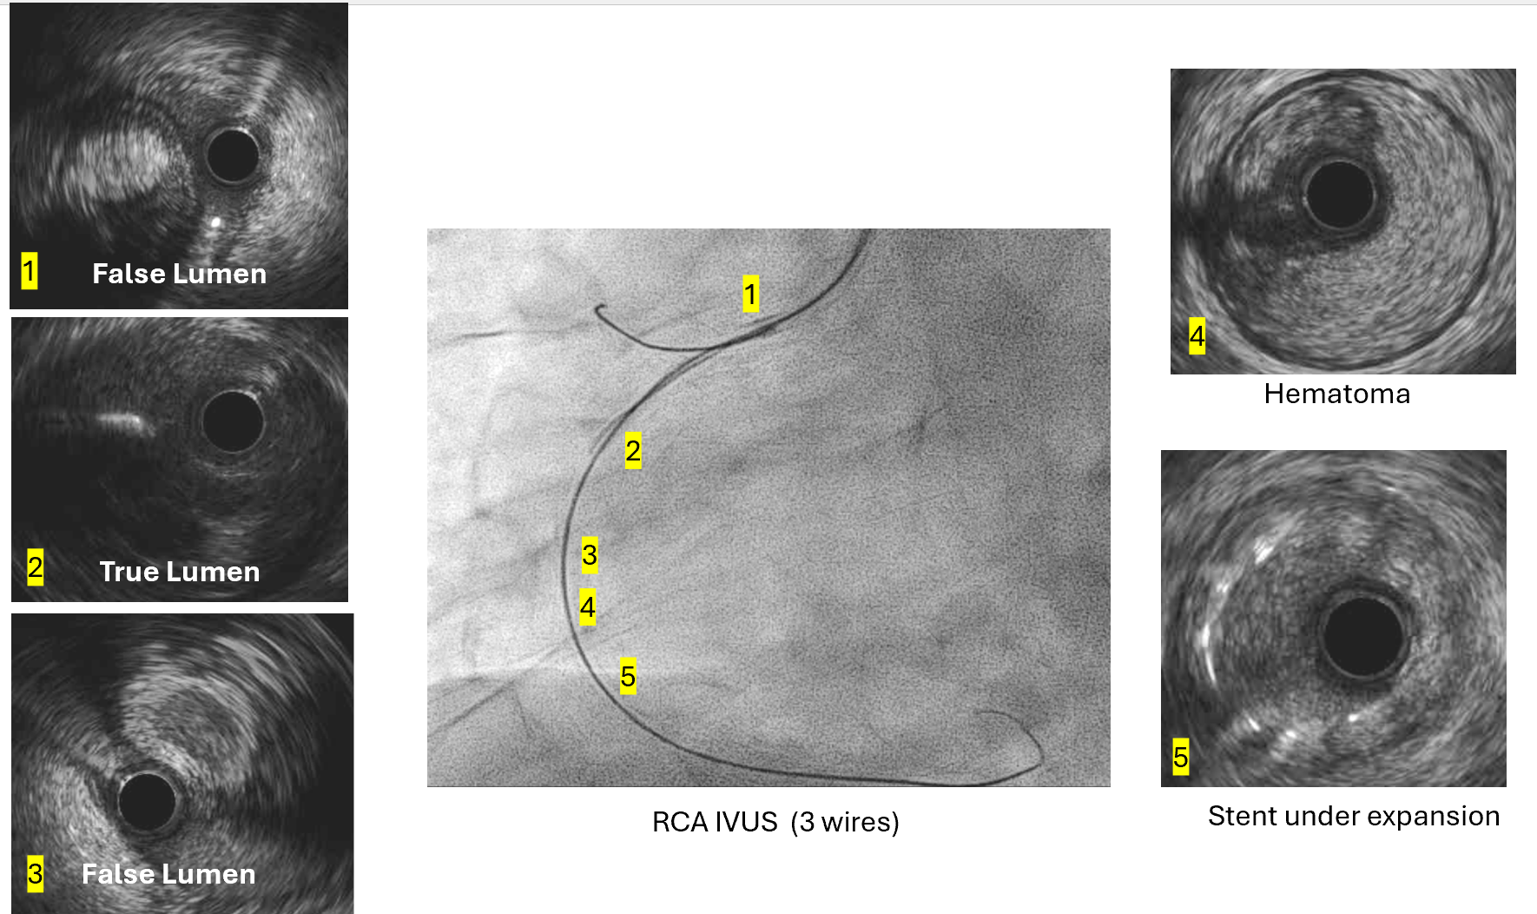

The SAL1 guiding catheter was unstable, jumping in and out the ostium. We deployed PK Papyrus 2.5 x 20 mm stent graft to dRCA quickly and planned to deployed another DES to p-dRCA. However, the patient agitated and the whole system was removed, leaving severe spiral dissection, starting from the ostium to middle RCA.We tried to wire FC, XTA and sion balck to true lumen but fail. Switched to 6F JR guiding but still fail.We wired FC to distal RCA with parallel wire technique and checked IVUS. The distal wire was over true lumen, but false lumen wiring was noted since proximal RCA.We wired XTA to true lumen under IVUS image. Then true lumen wiring was completed.We dilated with 1.5 balloon. Followed by Ryurei 2.50 x 15 mm to mRCA.We deployed Ultimaster Tansei 3.00 x 38 mm and Ultimaster Tansei 4.00 x 18 mm to p-dRCA.Post-dilated with 3.0, 3.5, and 4.0 NC balloon to RCA.The final IVUS showed well stent expansion.The final flow is good. We closed the procedure smoothly.